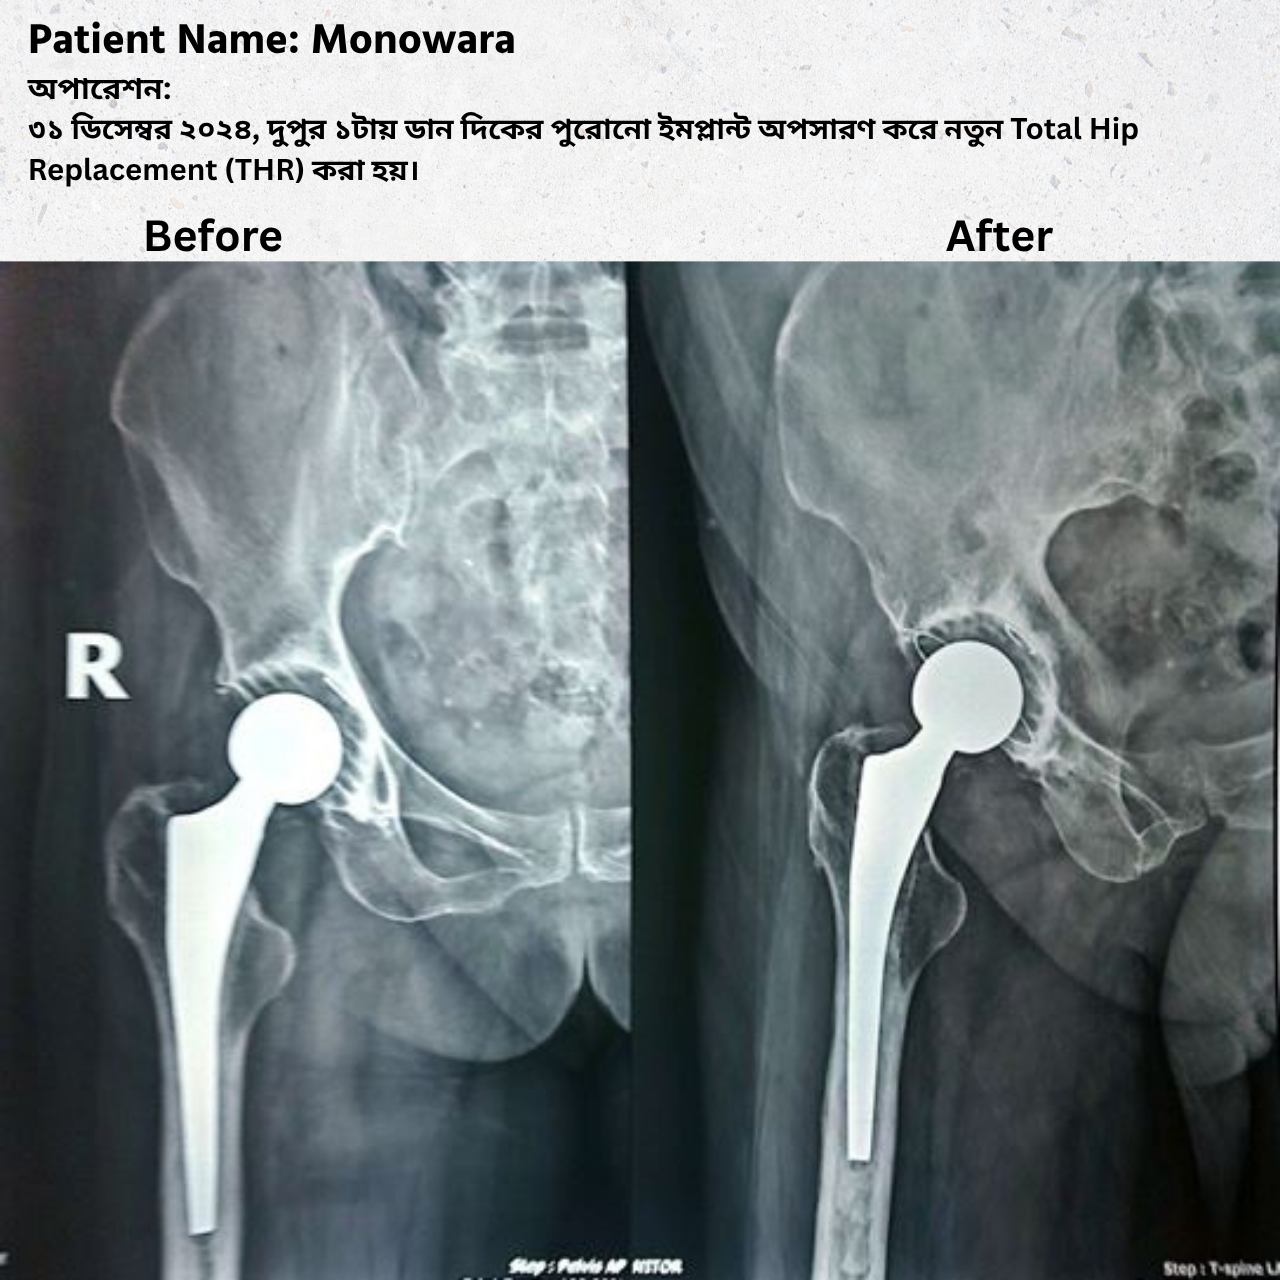

Operation